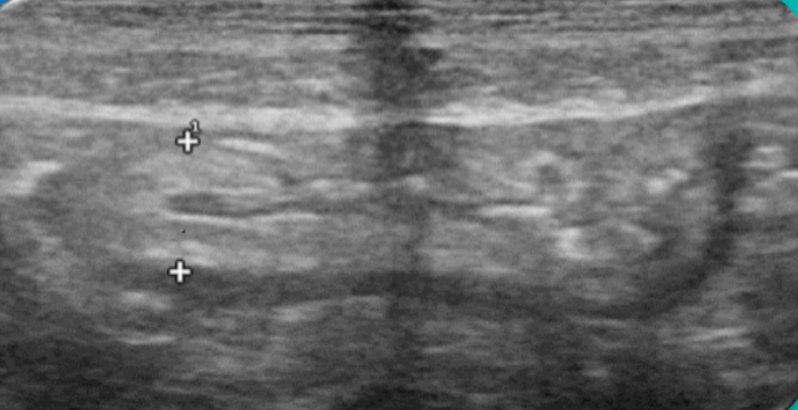

Expondremos la utilidad de la EC como herramienta en el manejo de los pacientes con diferentes tipos de dolor que atiende el Médico de Familia en las consultas diarias, urgentes, e incluso en los domicilios, en diversos escenarios clínicos a los que podemos enfrentarnos en nuestra práctica clínica habitual, desde un dolor visceral (abdominal, torácico, urológico o ginecológico), un dolor músculo-esquelético (traumático o no, con sospecha de fractura u osteoartrósico incapacitante), un dolor vascular (sospecha de trombosis venosa profunda, trombosis arterial aguda, aneurismático); ayudando a obtener una información crucial con un método no invasivo que nos ayudará a reducir la incertidumbre y orientar mejor el diagnóstico de nuestros pacientes e incluso nos podrá ser muy útil como herramienta con fines terapéuticos como en el caso de las infiltraciones ecoguiadas.